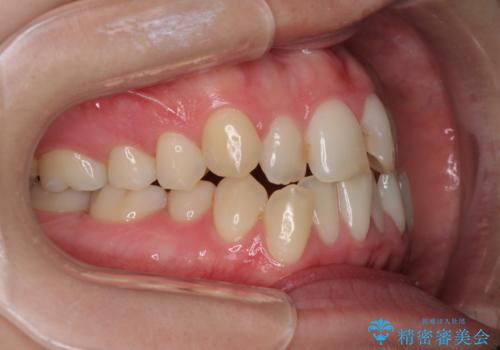

前歯のクロスバイトを治したい インビザラインによる矯正治療

- 前歯のデコボコとクロスバイトを治したいとのことで来院された患者様です。

上下顎ともに歯列全体の側方拡大とIPR(歯と歯の間を削る)によってデコボコとクロスバイトが解消するように設計し、インビザラインにより治療を行うこととしました。

下顎骨の左側への骨格的なずれが強く、上下の正中の位置合わせや奥歯の咬み合わせ構築に苦労しました。